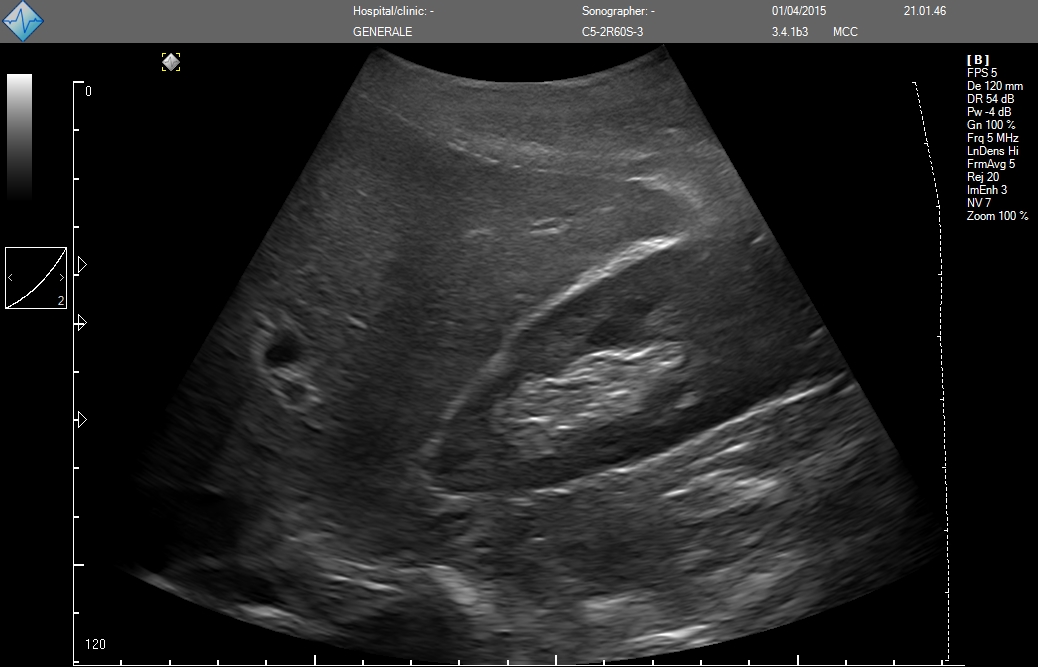

MicrUs Pro-C60S (конвексній, 2-5 МГц, R60 мм)

ЗДЕСЬ Вы можете посмотреть реальные кинопетли с аппарата УЗИ MicrUs Pro.